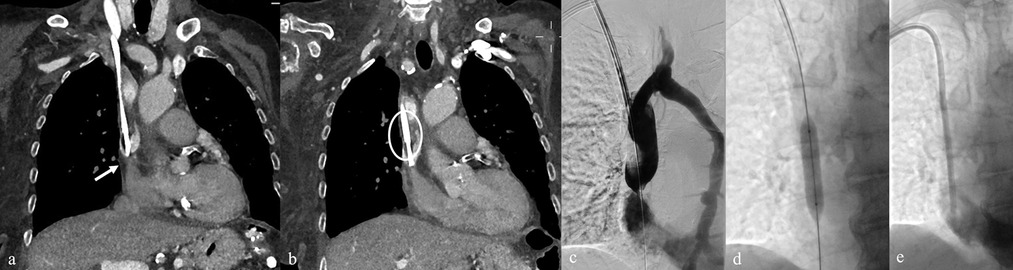

Background: Tunneled cuffed catheter (TCC) remains a crucial vascular access option for patients undergoing hemodialysis, particularly in those who are not candidates for arteriovenous fistulas or grafts. However, placement carries immediate and delayed complications. Objective: This narrative review aims to provide a comprehensive overview of the complications encountered during and after the placement of a TCC for hemodialysis, highlighting current evidence, risk factors, prevention strategies, and management approaches. Methods: A critical selection of relevant literature was performed through PubMed and Scopus databases, focusing on articles published in the last two decades. Particular attention was given to studies reporting on mechanical, infectious, thrombotic, and late-onset complications, as well as technical factors influencing outcomes. Results: Complications of TCCs can be classified as immediate (e.g., arterial puncture, pneumothorax, bleeding), early (e.g., catheter malposition, exit-site infections), and late (e.g., central venous stenosis, catheter-related bloodstream infections, thrombosis). Patient-and procedure-related factors increase risk. Ultrasound and fluoroscopy, strict sterility, and timely management reduce complications rates. Conclusion: TCCs are indispensable in selected patients, but understanding their complications is key to patient safety and outcomes. Optimal outcomes depend on accurate patient selection, operator expertise, and standardized post-placement care.